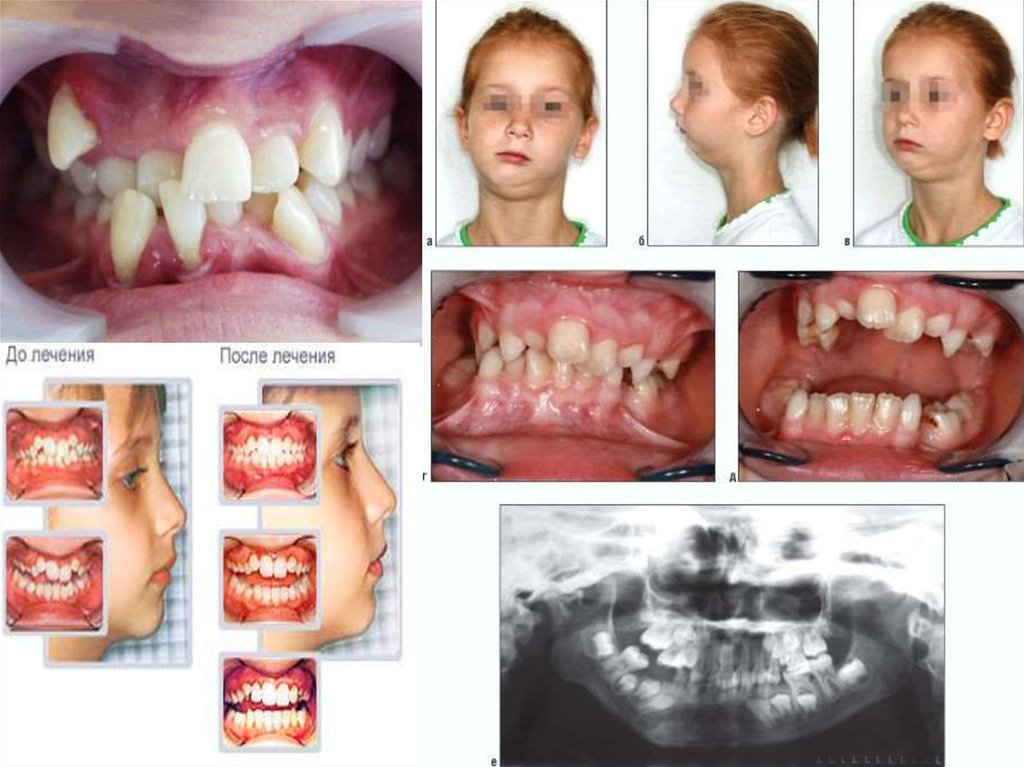

13.

6-7

жасында, тістердің тығыз орналасуы

және жұмсақ тіндердің аномальды бекуі

көрінуі мүмкін.